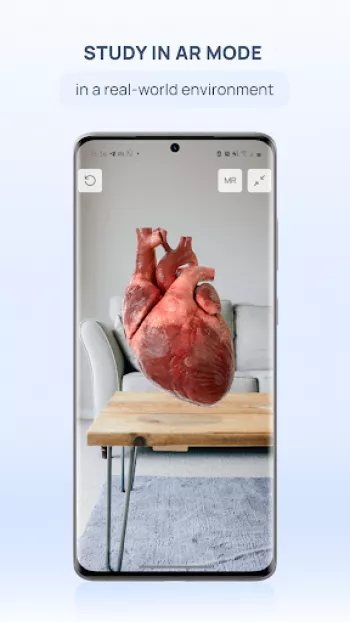

VOKA 3D Anatomy & Pathology

Factory of innovations and solutions LLC